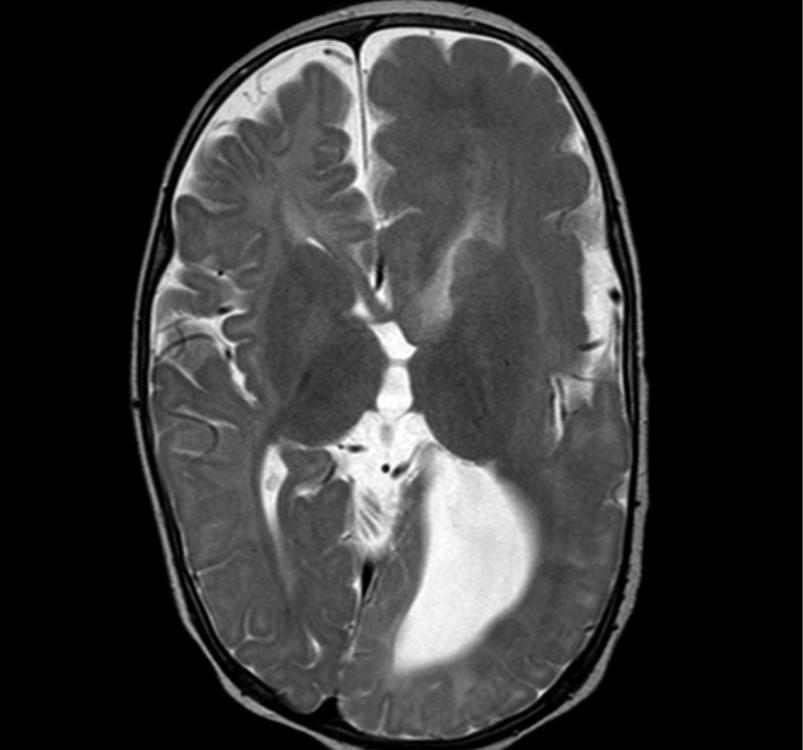

The image below shows an enlarged right hemisphere, with thickened cortex, blurring of the grey-white matter junction and abnormal signal in the white matter. The right basal ganglia is abnormal in structure and orientation. Ventricular size and morphology is abnormal, and the occipital lobe extends across the midline.

hemimegalencephaly